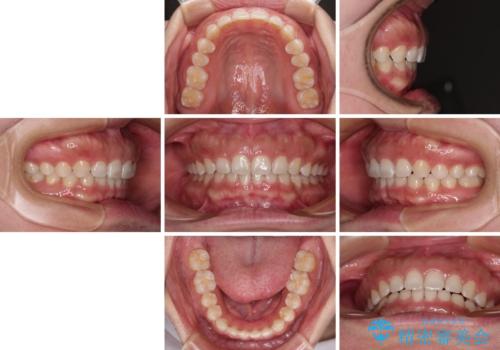

【モニター】ディープバイトを治す ワイヤー装置による矯正治療

- 顎が疲れるほどのディープバイトを気にして来院された患者様です。

手前に傾斜している奥歯を直立させながら、歯列全体の平面を均一に整えることでディープバイトを改善していくこととしました。

ディープバイトは咬合力が強いことが特徴であり、より良い仕上がりとするために、臼歯部のコントロールを行いやすいワイヤー装置を用いて矯正治療を行うこととしました。

ディープバイトが改善されたことで、食いしばりしかできなかった状態からスムーズな歯ぎしりができるようになりました。